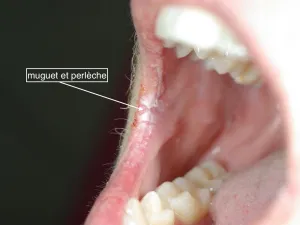

• Perlèche : cela correspond à une inflammation des commissures labiales (coins des lèvres), unilatérale ou bilatérale, avec une fissure rouge, macérée et douloureuse.

• Du muguet buccal qui se présente sous forme de plaques rouges à l’intérieur des joues, recouvertes d’un enduit blanchâtre qui se détache facilement au raclage.

Toutes ces anomalies peuvent être isolées ou associées.